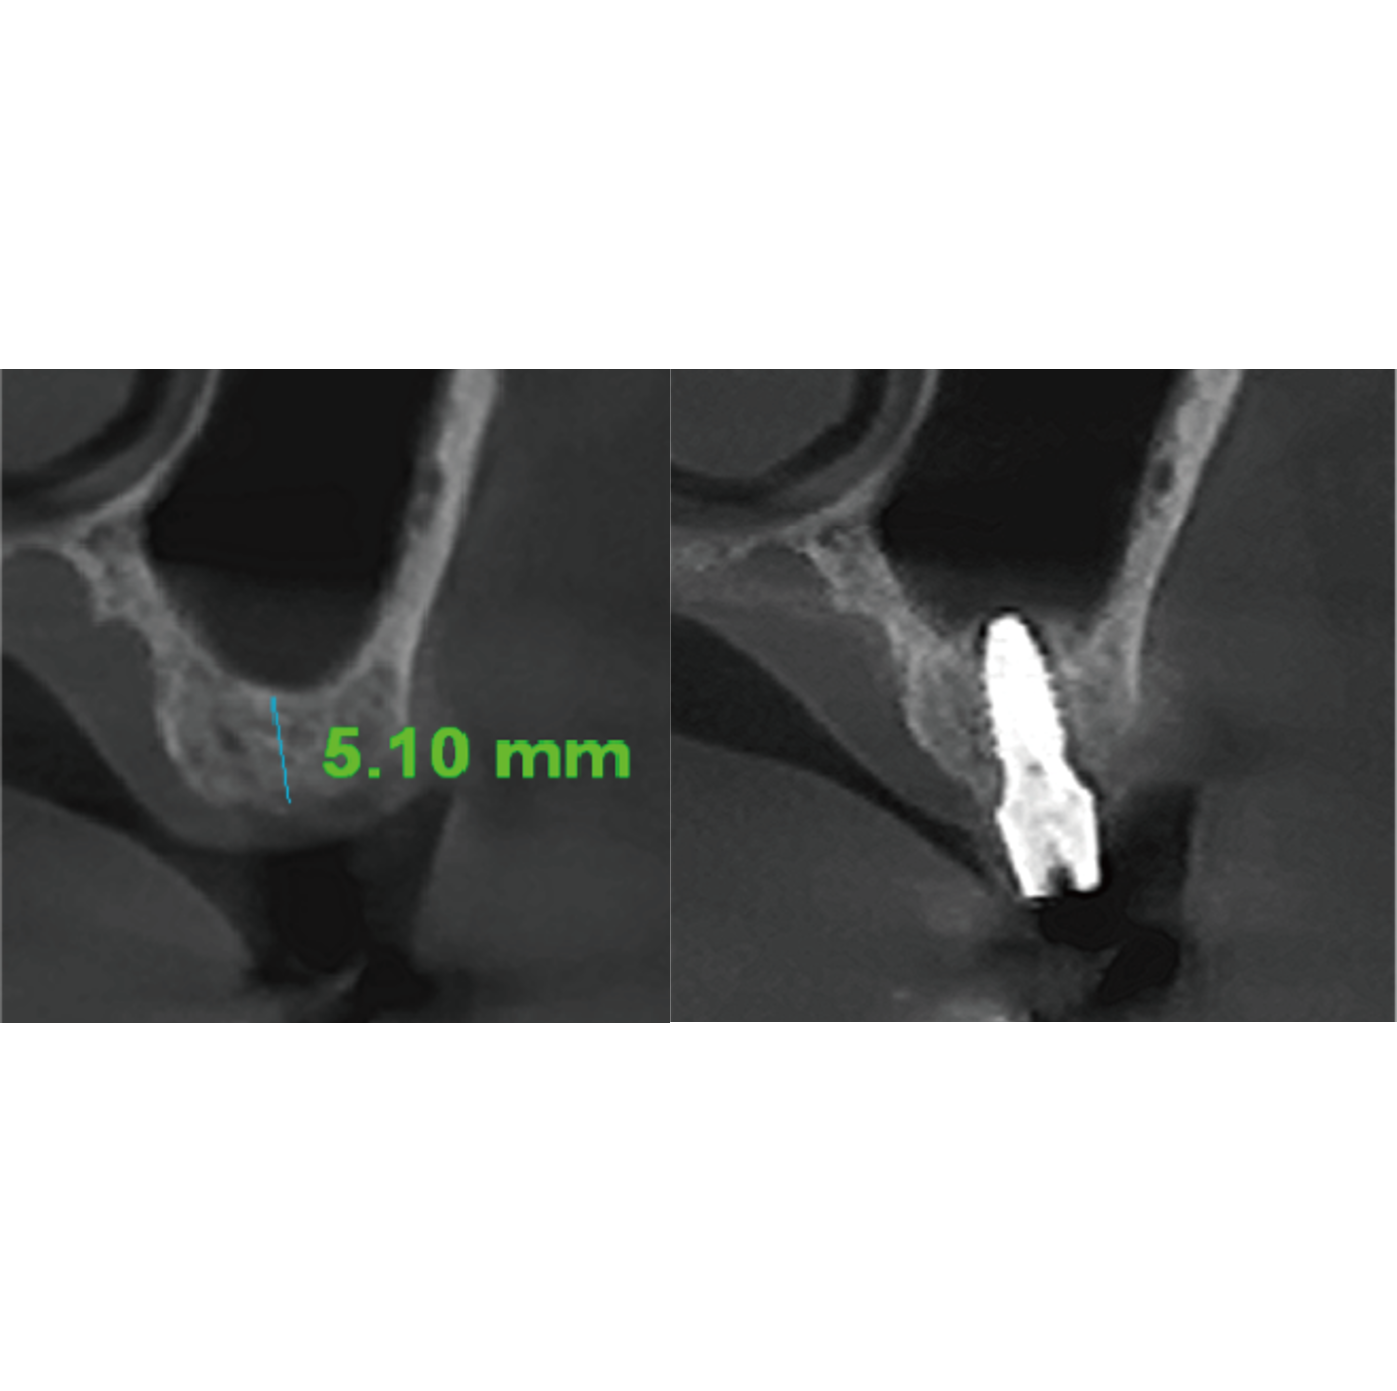

Lateral ApproachA flexible approach that allows access from multiple angles, even in severely limited bone conditions.

Lateral access is possible with minimal window formation, enabling controlled access and dissection.

Improved visibility and handling in challenging cases help reduce the risk of membrane perforation.